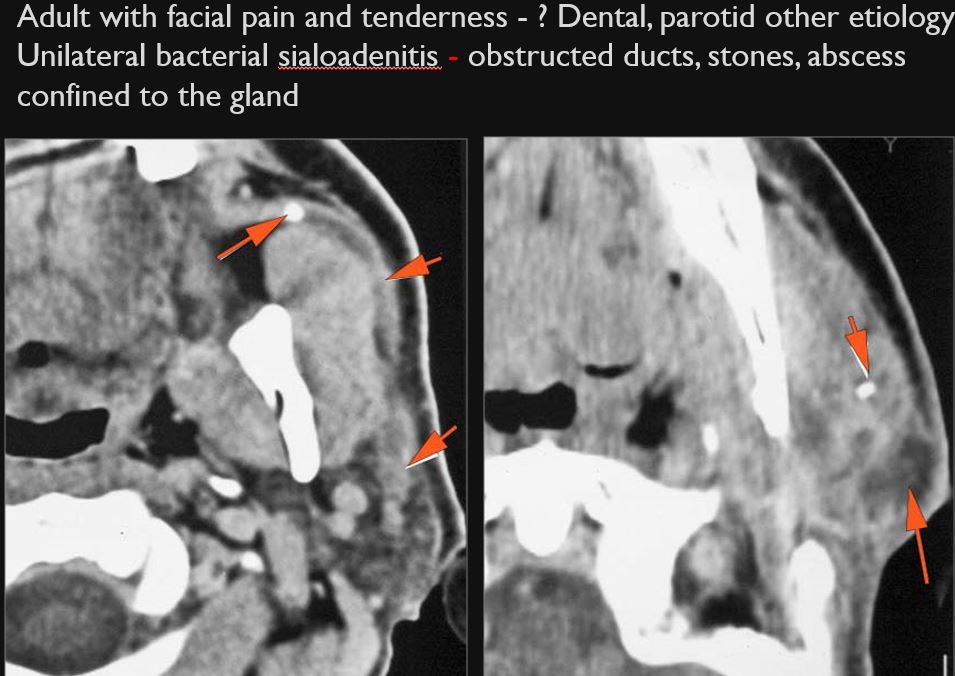

There is a developing abscess within the parotid gland.

The parotid ducts and/or intraglandular ductal systems are dilated and/or with evidence of intraductal stones other causes of obstruction.

There is edema (cellulitis) and/or abscess within the fat surrounding the parotid gland and/or of the masticator space or other adjacent spaces.